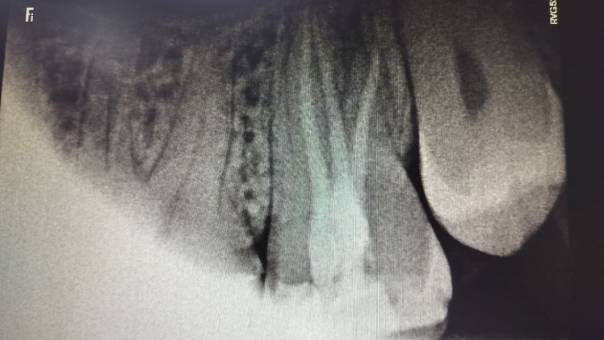

Clinical and Radiographic Findings:

On examination, mild tenderness was noted when

tapping on tooth 27. A radiographic evaluation

revealed that the distal canal of the tooth had been

inadequately treated and left unfilled. This had led

to a localized periapical infection.

Locating the distal canal

Unfilled distal canal pre-operation